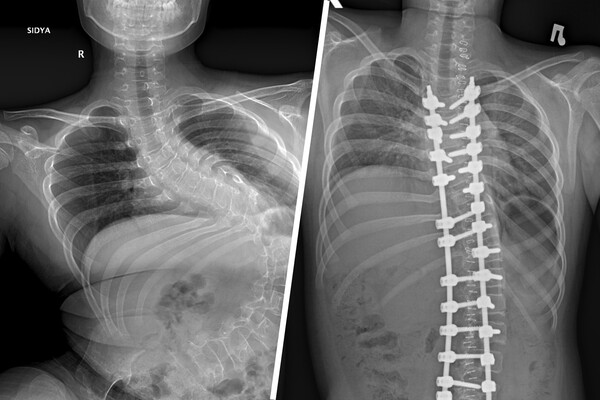

Российские врачи прооперировали мальчика с критическим искривлением позвоночника после ДТП

В Новосибирске врачи исправили искривленный после ДТП позвоночник школьника

В Новосибирске врачи НИИТО им. Я.Л. Цивьяна помогли 12-летнему мальчику, который десять лет жил с сильным искривлением позвоночника, полученным в автомобильной аварии.

«Первым этапом хирургического лечения стала коррекция деформации позвоночника, поскольку она достигла уже критических значений — более 140 градусов искривления. Без своевременно выполненной операции сколиоз прогрессировал бы дальше, и мальчик не смог бы даже сидеть», — рассказал врач больницы Александр Васюра.

Вмешательство длилось четыре часа: за это время ребенку скрепили позвоночник металлической конструкцией, скорректировав деформацию до 32 градусов.